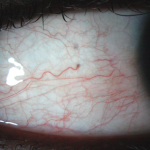

RedAI

Segmentation automatique des vaisseaux, quantification et grading de la rougeur de l’oeil